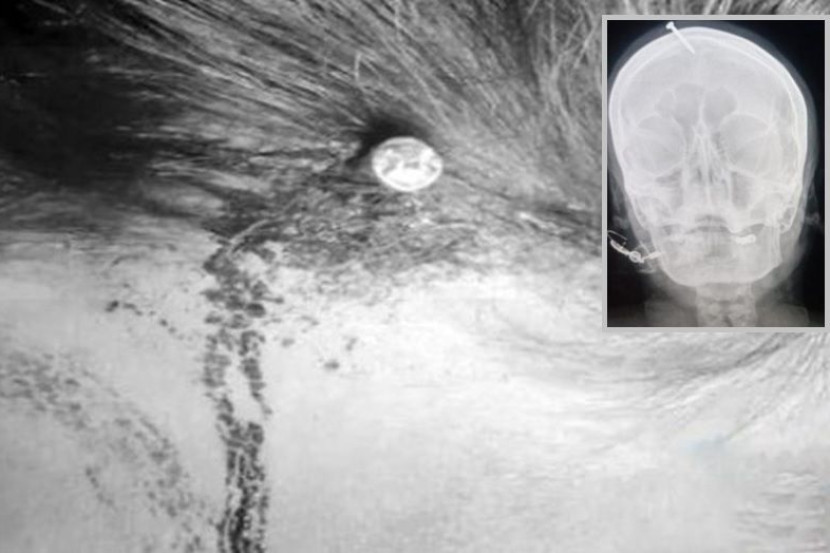

Imbasan X-ray menunjukkan paku sepanjang lima sentimeter itu menembusi bahagian atas dahi wanita tersebut.

"Dia sedar sepenuhnya, tetapi mengalami kesakitan yang amat sangat," jelas Dr Khan, yang mengeluarkan objek itu.